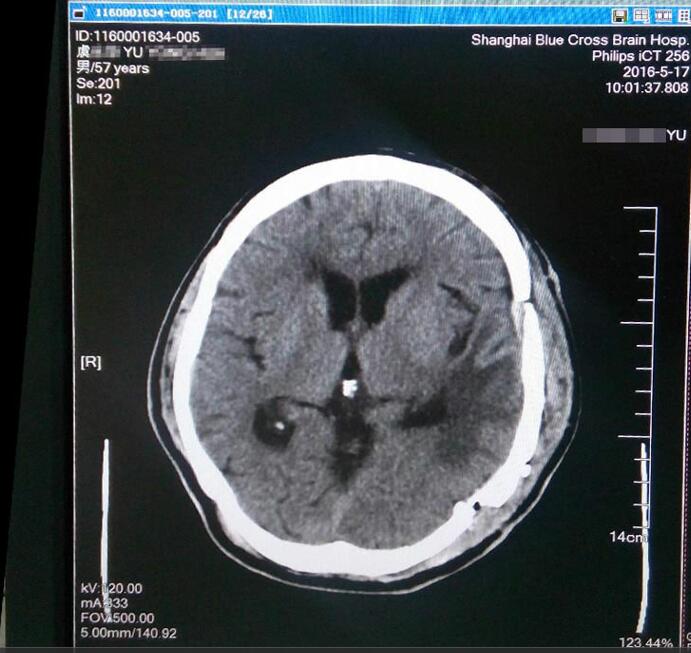

沈建康教授为虞文军成功施行巨大肿瘤切除术

术后MRI显示肿瘤已消失